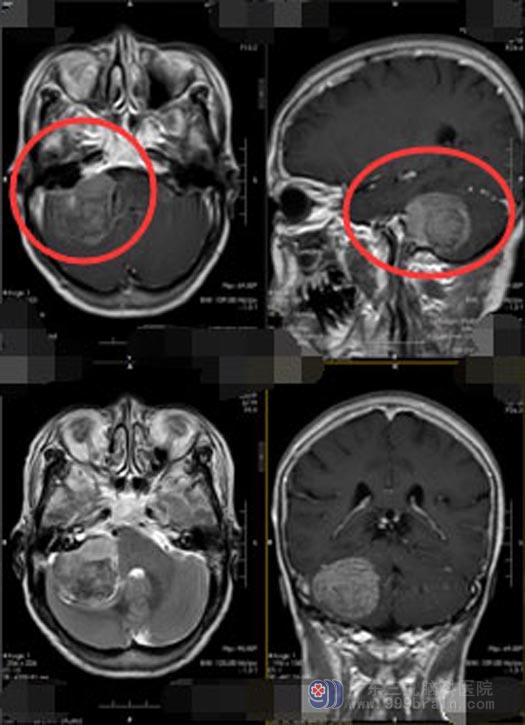

徐阿姨住院后查体:视力、视野基本正常,右耳听力较差,头颅MRI报告提示:右侧桥小脑角区占位,头颅CTA显示:右侧桥小脑角区占位性病变大部分钙化,实性部分血供一般,考虑脑膜瘤。主管医生卢建侃和徐阿姨家属沟通病情:颅内的肿瘤体积较大,周围脑组织水肿明显,正常组织受到压迫引起听力减退、头晕等症状,有手术指证,需要手术切除,但是这个肿瘤不仅位置特殊、体积巨大,累及重要神经和血管,而且已经钙化,比较坚硬。出现钙化说明脑膜瘤已经存在很长时间了,这大大增加了手术切除难度,面临的手术风险也成倍增加。陈阿姨家人说:来医院之前,他们已经了解过此疾病的相关知识,正是因为知道手术的难度和风险,才专门来到了广东三九脑科医院。

排除手术禁忌症后,鲁明副院长带领神经外五科医生团队在全麻下为徐阿姨实施了“右侧桥小脑角区脑膜瘤切除术”。乙状窦后入路,术中可见硬膜张力高,白色肿瘤组织质硬,钙化严重,血供丰富,肿瘤上至三叉神经,下达末组颅神经,与面听神经及脑干明显粘连,在显微镜下分块切除肿瘤,大小约4cm×4cm×3cm,相邻神经血管保护良好,保留面听神经,手术顺利。

▲手术前